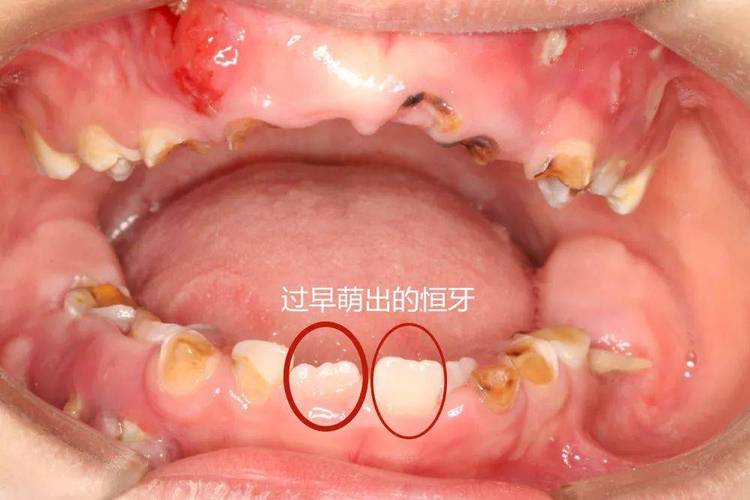

(图片来源网络,侵删)